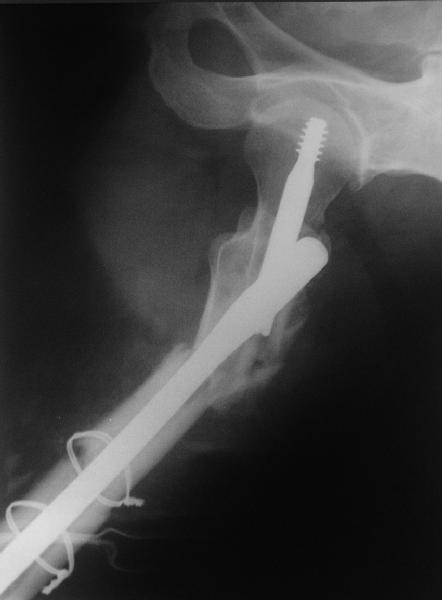

Изначально была выбрана не правильная точка введения стержня, в связи с чем в конце, я подчеркну, в конце операции произошло из-за напряжения между прокимальным концом канала бедра и стержнем разрушение в/3 бедра.

Проволока наложена потому, что при введении штифта не прошли эту зону римером и произошли сколы на концах отломков.

В общем, сделали. См. приложение.

Длина и из-за этого ось получились не совсем такие, как хотелось бы, все-таки срок после той операции уже 6 недель. Может быть, стоило провести дистракцию аппаратом неделю-другую. Заранее спасибо за комментарии и критику.